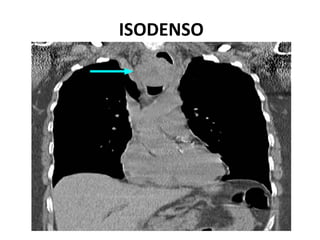

HIPERDENSO E HIPODENSO

ISODENSO